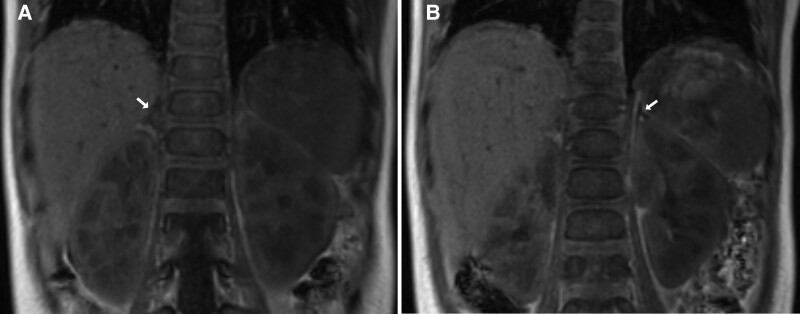

Familial glucocorticoid deficiency (FGD) is a rare autosomal recessive disorder that causes isolated glucocorticoid deficiency. Here, we report on 22-month-old twin females of Native American ancestry who presented within 1 week of each other in adrenal crisis and were ultimately diagnosed with FGD because of a novel pathogenic variant, c1924G>T (p. Gly642*), in the nicotinamide nucleotide transhydrogenase (NNT) gene. This is the first report of FGD in a Native American population. The process of reaching the final diagnosis was complicated by several social determinants including geographic rurality, access to subspecialists, financial constraints, and challenges obtaining approval for genetic testing despite having insurance. Concerted efforts by the family, the local pediatrician, the Indian Health Service, and our tertiary care pediatric health system were required to reach the final diagnosis and develop an appropriate plan of care for the patients.